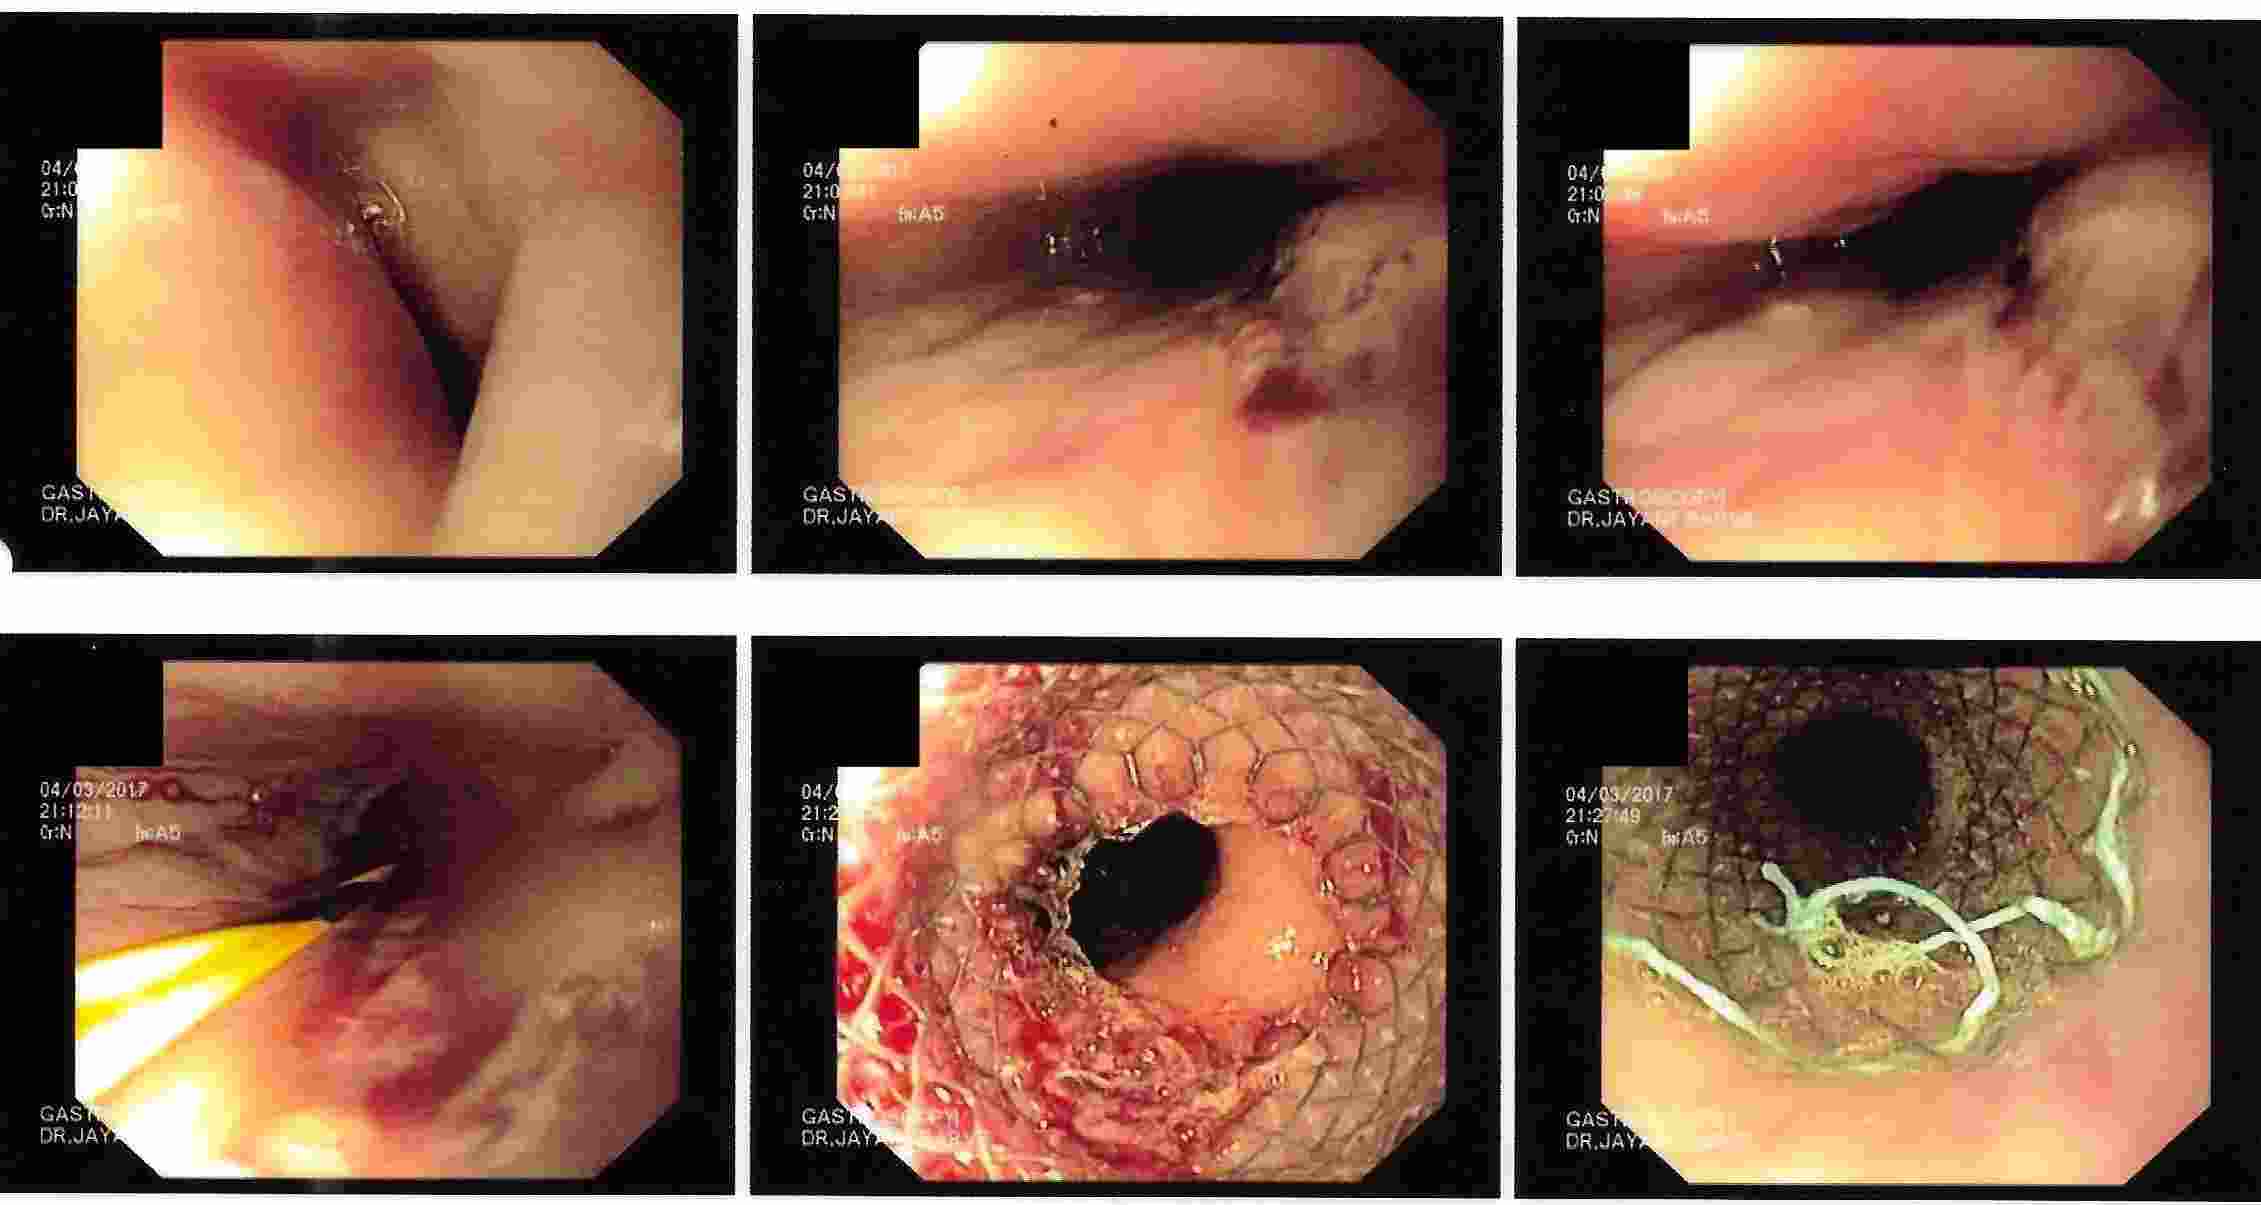

3. Difficulty in swallowing : This is considered as a serious symptom at any age group.

Difficulty in Swallowing

This can be due to severe acidic ulcerations, narrowing of the food passage due to non cancer or

cancerous lesion or pressure on the food pipe from outside.

Cancerous Lesion - Balloon Dilatation as a Palliative Treatment

Cancerous Lesion - Metal Stent as a Palliative Treatment

Cancerous Lesion - Metal Stent as a Palliative Treatment

Cancerous Lesion - Metal Stent as a Palliative Treatment

Strong contractions of the food pipe is known as dysmotility of esophagus and an unusual condition known

as Achalasia Cardia due to powerful contraction of the valve of the esophagus at its lower end which

can cause difficulty in swallowing.

Achalasia Cardia - Balloon Dilatation

Achalasia Cardia - Balloon Dilatation

Achalasia Cardia - Balloon Dilatation

Achalasia Cardia - Balloon Dilatation